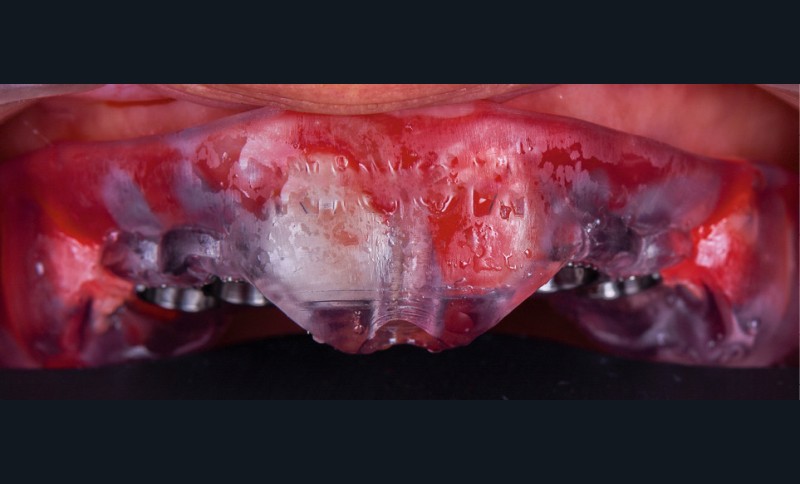

- installation du guide et forage implantaire à travers les canons de forage (fig. 4) ;

- mise en place de 4 implants Primetaper Dentsply (diamètre 3.6/ longueur 13 mm) ;

- vérification du positionnement implantaire et du torque à la clef dynamométrique : 45 Newton ;

- mise en place d’une vis de couverture sur les implants ;

- comblement du gap à l’aide d’un biomatériau combinant hydroxyapatite et trame collagénique (Ossix Bone Dentsply) ;

- dévissage des vis de couvertures ;

- mise en place des vis de cicatrisation (fig. 5) ;